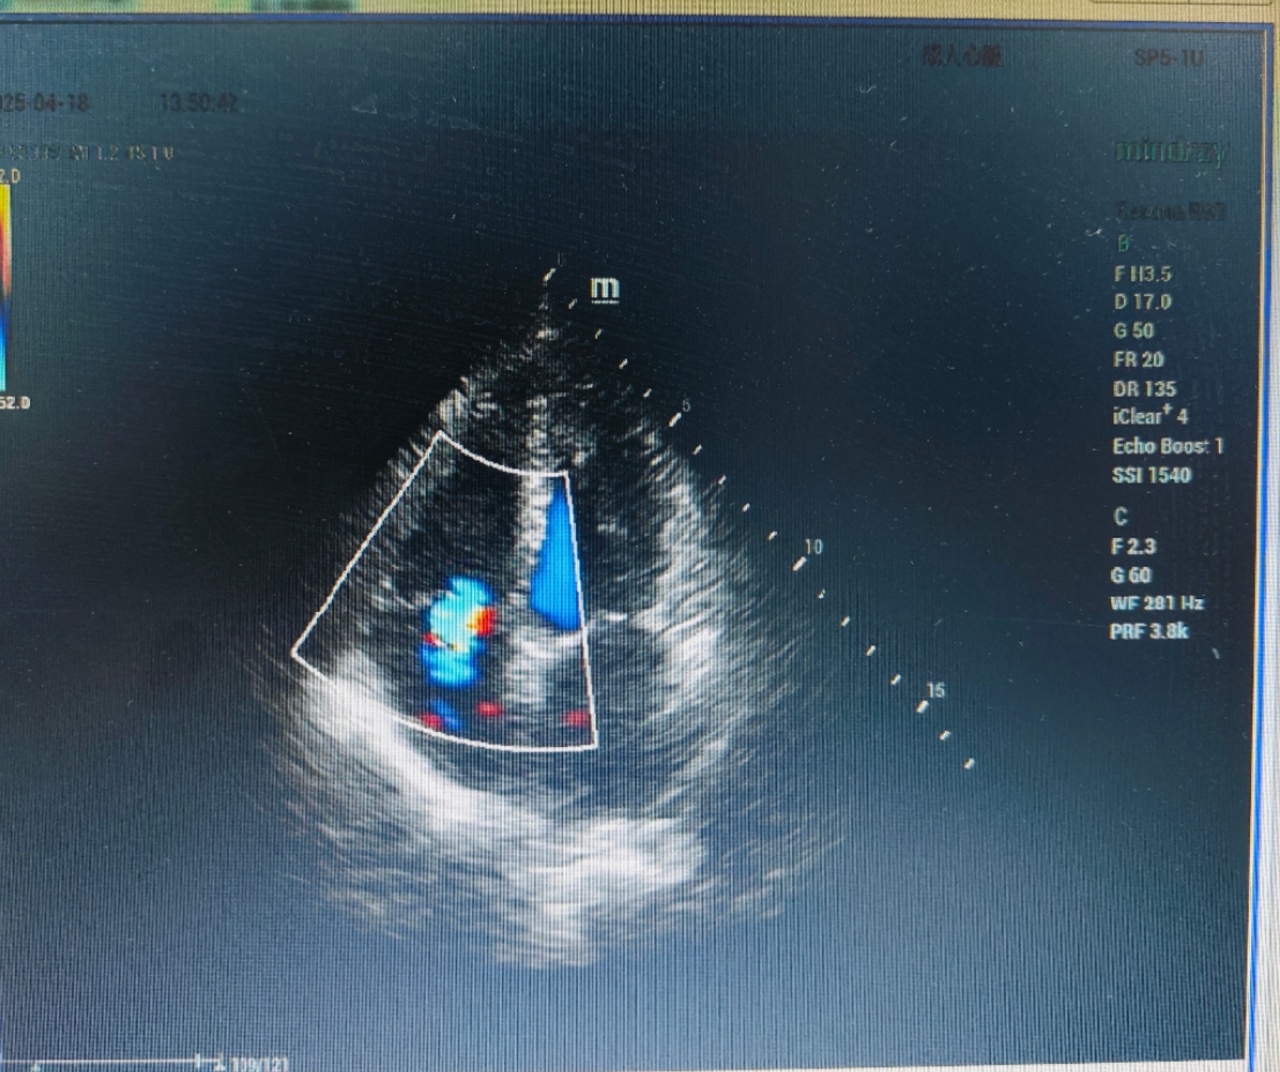

心脏超声(又称“超声心动图”)是一种利用超声波技术无创检查心脏结构和功能的影像学方法。它如同给心脏做“实时直播”,能清晰显示心脏大小、瓣膜开闭、心肌运动及血流状态,是诊断心脏病的重要工具。

2. 瓣膜疾病:评估二尖瓣、主动脉瓣等是否狭窄或关闭不全。

3. 心功能评估:测量心脏射血分数(EF值),判断心力衰竭程度。